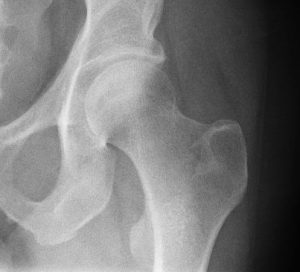

The talk was full of facts and sometimes rather alarming figures. Such as 1 out of 2 women over 50 will have a bone fracture. Plus once you have one fracture, a second one is highly likely. This leads to great personal cost, and costs to the NHS. So preventing this and recognising you may be at risk of fractures as a result of osteoporosis is very important.

Dr Dolan explained in her talk how to recognise symptoms of fragile bones, and outlined measures to take preventative measures, such as high impact exercise and taking Vitamin D.